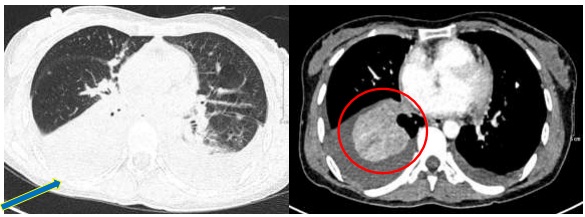

- Chụp cắt lớp vi tính ngực: Rốn phổi phải có đám thâm nhiễm kích thước 28x32mm, ranh giới không rõ, gây hẹp lòng và cắt cụt một số nhánh phế quản thùy dưới. Thùy trên phổi phải có nhiều nốt đặc, đám mờ kích thước lớn nhất 14x8mm. Dịch màng phổi hai bên, dày 28-30mm. Dịch màng ngoài tim dày 6mm. Thâm nhiễm mỡ lan tỏa trung thất, hạch trung thất kích thước lớn nhất 13x8mm.

Hình 1: Hình ảnh cắt lớp vi tính lồng ngực: Hình ảnh rốn phổi phải có đám thâm nhiễm kích thước 28x32mm

Hình ảnh dịch màng phổi hai bên, dày 28-30mm. Dịch màng ngoài tim dày 6mm. Thâm nhiễm mỡ lan tỏa trung thất, hạch trung thất kích thước lớn nhất 13x8mm

- Chụp cắt lớp vi tính ngực:Khối vùng rốn phổi phải gây xẹp phổi kích thước 28x32mm. Dịch khoang màng phổi phải dày 50mm. Khống thấy hạch to trung thất

So sánh hình ảnh cắt lớp vi tính ngực trước và sau điều trị 3 chu kỳ: